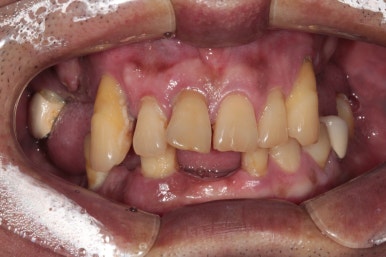

딱 봐도 치아가 많이 없으신 50대 남자 환자분입니다.

어떻게 그 동안 식사를 하셨는지 단번에 걱정이 되었던 분.. 개원 후 얼마 되지 않아 방문해셨던 분이라 더욱 기억에 남는 분입니다.

사실 보고 있자니 마음이 심란합니다.

큰 어금니는 한개 밖에 남지 않았고, 그나마 작은 어금니도 여러개 소실되어 있네요.

아래 앞니도 없어졌고.....

정면부터 비교도 안되게 좋아지신 것을 보실 수 있을겁니다.

위 앞니는 지르코니아 크라운으로, 아래 앞니는 지르코니아 브릿지로 새로 제작하여 적절한 overjet과 overbite를 형성하였고 상당히 자연스러운 외형을 갖춘 것을 보실 수 있을거에요.

또한 앞니를 크라운으로 제작하면서 치아의 색상도 보다 톤업해드렸고, 치아 배열도 가지런하게 그리고 치아 사이 공간도 모두 닫아드려 정말 한결 젊어졌다는 느낌이 듭니다.